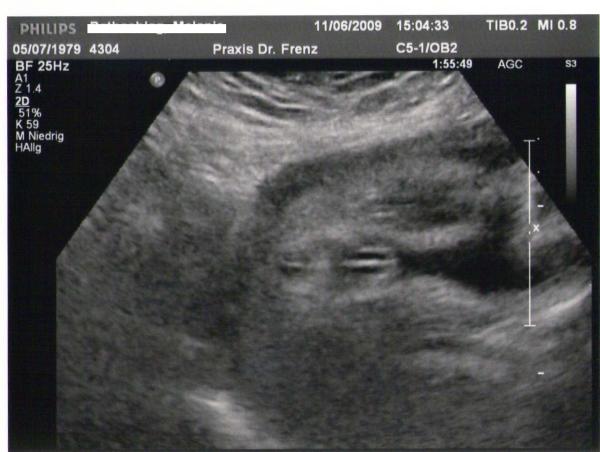

Das ist mein kleiner Junge.